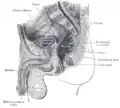

Сагиттальное сечение мужского таза